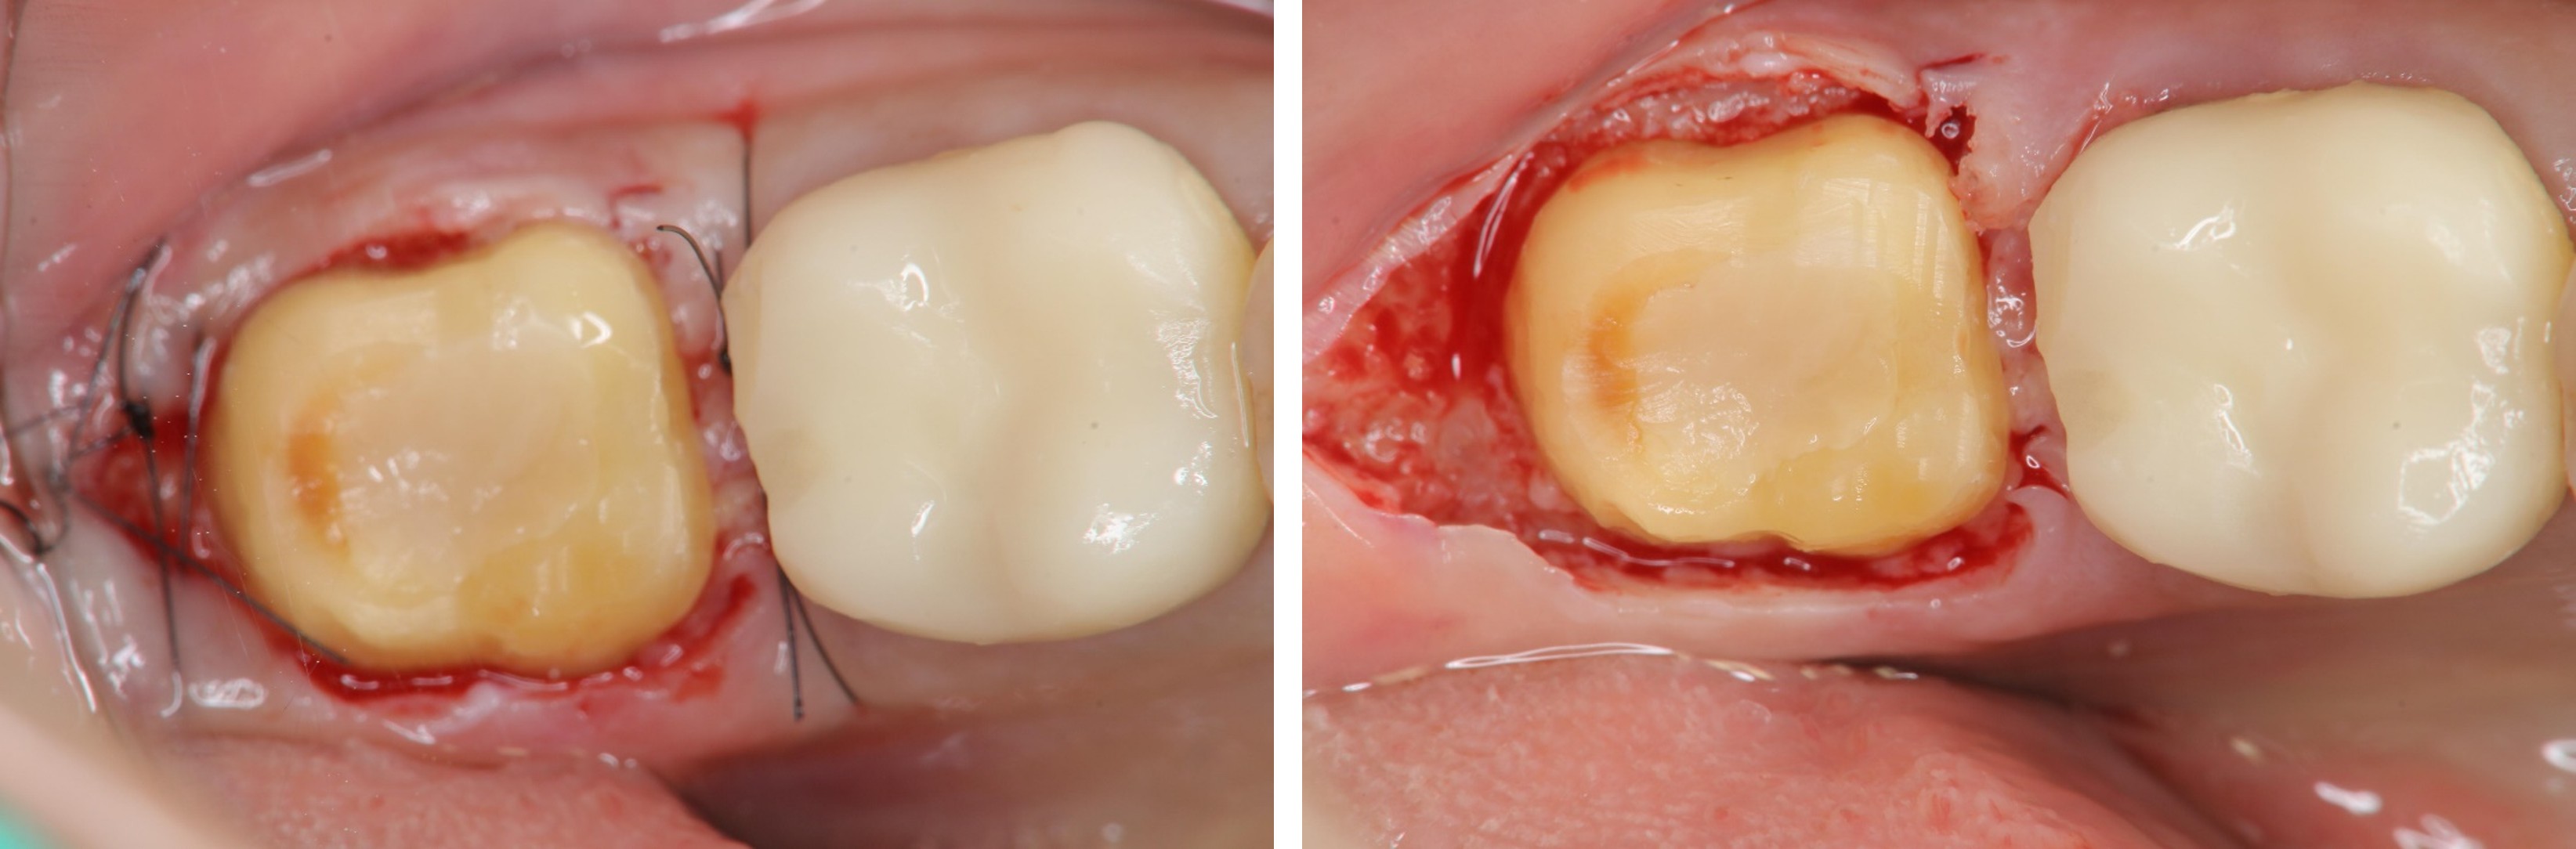

牙冠增長手術-#36

牙冠增長手術-#37